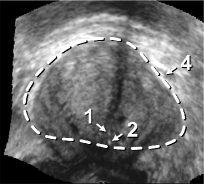

The framework was validated on 278 registrations of 295 US volumes from 17 patients. The 17 reference images were acquired shortly before the intervention, and the tracking images were acquired after a biopsy shot. The clinical protocol was approved by the ethical committee of the XXX hospital, Town, Country, and all patients consented to participate to the study. The images were acquired with a GE Voluson and a RIC5-9 endorectal US probe. The algorithms were executed on a 4-core 2.6Ghz processor. In order to provide a reference gold standard for the evaluation of registration accuracy, experts manually segmented 467 point fiducials that were clearly identifiable on multiple images (e.g. calcifications and cysts). The distances between fiducial pairs were measured after registration to estimate the local accuracy. Note that the unavoidable segmentation error increases the measured error in average; this approach hence underestimates accuracy. Accuracy was computed for all registrations that were qualified as valid by experts after visual inspection, which represent 97,8%percent\% of the registrations. The results for both rigid and elastic registration are given in Tab. 1, and a visual illustration of the registration performance is given in Fig. 2. Fig. 3 shows 3D biopsy maps created with our biopsy tracking system.

Figure 2: Fig. (a) shows a prostate volume with calcifications [1,2]. Fig. (b) shows a second volume after rigid registration; low probe pressure led to the low contrast zone [3]. Fig. (c) shows the 3D elastic registration with standard SSD; the whole prostate is dragged towards zone [3]. Fig. (d) shows the 3D intensity shift filtered, inverse consistent elastic registration; the strong intensity differences between both volumes are correctly handled, the calcifications make appearance at the correct position (best viewed in PDF with zoom).